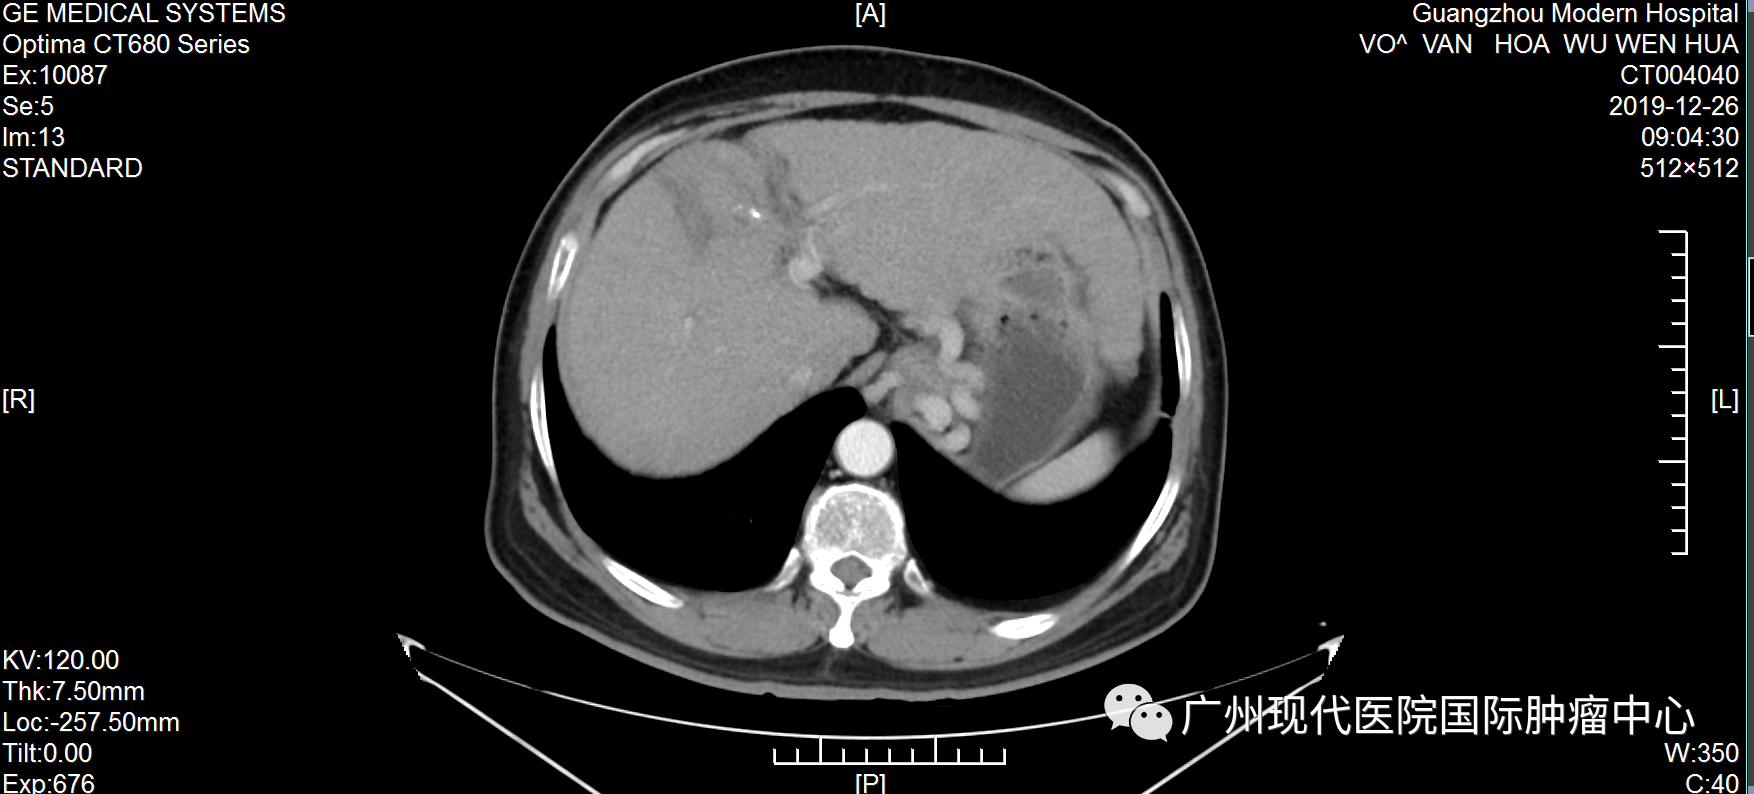

不愿做手術(shù), 弟子推薦好醫(yī)院 武文華自10歲起出家,年輕時,一直去各大佛寺學習佛教知識和游歷,直至1999年時確診丙肝,此后一直堅持吃藥治療。不曾想,時間的指針轉(zhuǎn)到2019年,丙肝惡化為肝癌。 2019年6月,武文華因反復勞累出現(xiàn)低熱,伴隨右上腹脹痛、頭痛等癥狀,且面部神經(jīng)受影響,尤其是下頜與唇部麻痹且疼痛。隨后,他到當?shù)蒯t(yī)院就診,做腹部CT檢查,初步診斷為肝細胞肝癌、肝硬化。當?shù)蒯t(yī)生建議做手術(shù),武先生不愿意開膛破肚,也擔心手術(shù)風險、術(shù)后感染等問題,于是拒絕越南醫(yī)生的治療方案。 武文華和妹妹及弟子合影 機緣巧合下,武文華的弟子了解到自己的一位親友在一家口碑很好的癌癥專科醫(yī)院——圣丹福廣州現(xiàn)代腫瘤醫(yī)院獲得了很好的治療,現(xiàn)在腫瘤已經(jīng)完全消失了。弟子把這家醫(yī)院推薦給武文華,告訴他不用開刀也能很好地治療癌癥,并給他介紹最新的微創(chuàng)技術(shù)?!安挥瞄_刀”這一技術(shù)優(yōu)勢深深地吸引了武文華,他很快找到胡志明辦事處咨詢,并在工作人員的幫助下來到廣州。 微創(chuàng)綜合治療, 讓他重獲新生 2019年7月,武文華來到圣丹福廣州現(xiàn)代腫瘤醫(yī)院。根據(jù)他的病情,醫(yī)院MDT醫(yī)療團隊研討決定,給予他綜合微創(chuàng)治療方案。 第一次住院期間,武文華先后接受介入治療、納米刀等微創(chuàng)治療。介入治療可以切斷癌細胞營養(yǎng)供給,抑制腫瘤生長,減少腫瘤轉(zhuǎn)移,直至徹底殺死腫瘤;而納米刀是一種全新的尖端腫瘤消融技術(shù),通過電極探針釋放高壓脈沖擊穿腫瘤細胞的細胞膜,形成多個納米級不可逆的電穿孔,破壞細胞膜,從而破壞癌細胞組織,使細胞快速凋亡。他曾經(jīng)的主治醫(yī)生馬主任表示,這個治療方案,非常適合武文華這種不愿接受傳統(tǒng)治療、甚至對放化療已經(jīng)產(chǎn)生耐受性的癌癥患者。 2019年武文華住院期間生活照 據(jù)了解,入院前,武文華體內(nèi)的腫瘤大小為70*60mm。經(jīng)介入栓塞治療和納米刀治療后,腫瘤縮小到22*16mm?;貞浿委熯^程,武文華表示:“因為不需要開刀,每一次微創(chuàng)治療都在半小時內(nèi)結(jié)束。做介入治療時,沒有任何痛感,第二天就可以下床。納米刀是在全麻的情況下做的,沒什么感覺?!?/span> 治療1個月后,肝部腫瘤明顯縮小 治療5個月后,腫瘤已基本消失 活動中,馬主任回憶稱:“他總共接受了5次介入治療和納米刀治療,綜合治療完成后,肝部的腫瘤基本消失,他頭痛發(fā)燒及面部神經(jīng)影響等問題也得到了解決?!蹦[瘤消失后,為了鞏固治療效果,他遵守醫(yī)囑再次入院并接受了免疫治療。 自2019年7月至今,武文華已經(jīng)抗癌成功5年了,這對于他的家人而言是一種莫大的幸福。他的妹妹欣喜地說:“此前在越南的醫(yī)院,醫(yī)生下結(jié)論說他不做手術(shù)只能活3個月,如果做手術(shù)成功率只有30%。時間證明我們選擇來廣州治療是對的,現(xiàn)在他每年仍然在越南定期檢查,結(jié)果完全穩(wěn)定,而健康的狀態(tài)現(xiàn)在已經(jīng)延長了5年,這是一個奇跡!” 醫(yī)患情暖人心, 定下十年之約 這是武文華第三次回到醫(yī)院。在采訪中,他表示:“我完成治療返回越南后,新冠疫情就爆發(fā)了,我像往常一樣進行寺廟的日常管理工作,還積極參加抗疫的工作,我很幸運能夠那么快地恢復健康,這要歸功于醫(yī)院的精心治療和護理。” 住院期間,因為面部神經(jīng)不適等癥狀,武文華被我院醫(yī)護人員悉心照料照顧,他為之動容并為他們創(chuàng)作了一首詩:“別時合影它日憶,此處高風妙可夸。天使殷勤通晝夜,良醫(yī)吐哺映蓮花。”談起寫詩的初衷,他說:“我曾經(jīng)在別的醫(yī)院治療過,后面依然選擇這里,是因為這里的醫(yī)生和護士都非常專業(yè),對病人熱情而周到?!?/span> 2019年,武文華出院時為我院賦詩及合影 活動中,武文華和主治醫(yī)生馬主任合影 他以親身經(jīng)歷,對其他患者強調(diào),腫瘤不是一種絕對導致死亡的疾病,而是一種慢性病。“現(xiàn)在我能夠正常地飲食,工作,還能進行體育鍛煉。如果你確診了癌癥,請不要灰心,不要悲傷,一定要遵守醫(yī)囑,相信自己可以恢復健康。” 抗癌明星的聚會中,馬主任仔細聆聽他的分享,不斷綻放出感動與欣慰交織的笑容。她難掩心潮澎湃,還定下一場“十年之約”:“看到武大師目前擁有這么健康的狀態(tài),我感到我們醫(yī)護人員所有的努力和付出都是值得的。希望十年后和大家再相聚!” 活動后,武文華還同其他抗癌明星們一起,體驗了一場精彩紛呈的廣州之旅。他們夜游珠江,體驗現(xiàn)代都市的繁華;結(jié)伴同游寶墨園,觀中華文化的博大精深。他們的癌后余生,正如腳下的路,徐徐綿延向前,充滿陽光! 微創(chuàng)治療技術(shù)簡介 納米刀:是一種全新的腫瘤消融技術(shù),源于不可逆電穿孔技術(shù),通過電極探針釋放高壓脈沖擊穿腫瘤細胞的細胞膜,形成多個納米級不可逆電穿孔,破壞細胞內(nèi)外平衡,使細胞快速凋亡。治療優(yōu)勢是時間短、 治療區(qū)域的血管、神經(jīng)等重要組織得以保留、安全可靠等。 1、具備創(chuàng)傷小、并發(fā)癥少、安全、恢復快的優(yōu)勢。 2、可適應更多復雜的病情,包括胰腺、肝、肺、腎、前列腺以及其他實體腫瘤 介入治療:在醫(yī)學影像設備引導下穿刺,利用特制導絲等精密器械,將比靜脈點滴藥物濃度高2~8倍的抗腫瘤藥物直接注入腫瘤內(nèi)部,同時對腫瘤的供血動脈進行栓塞,實現(xiàn)腫瘤縮小甚至消失的目的。 1、具備創(chuàng)傷小、并發(fā)癥少、安全、恢復快的優(yōu)勢。 2、適合采用傳統(tǒng)放化療效果不佳、不愿或不適合做手術(shù)等情況的患者。